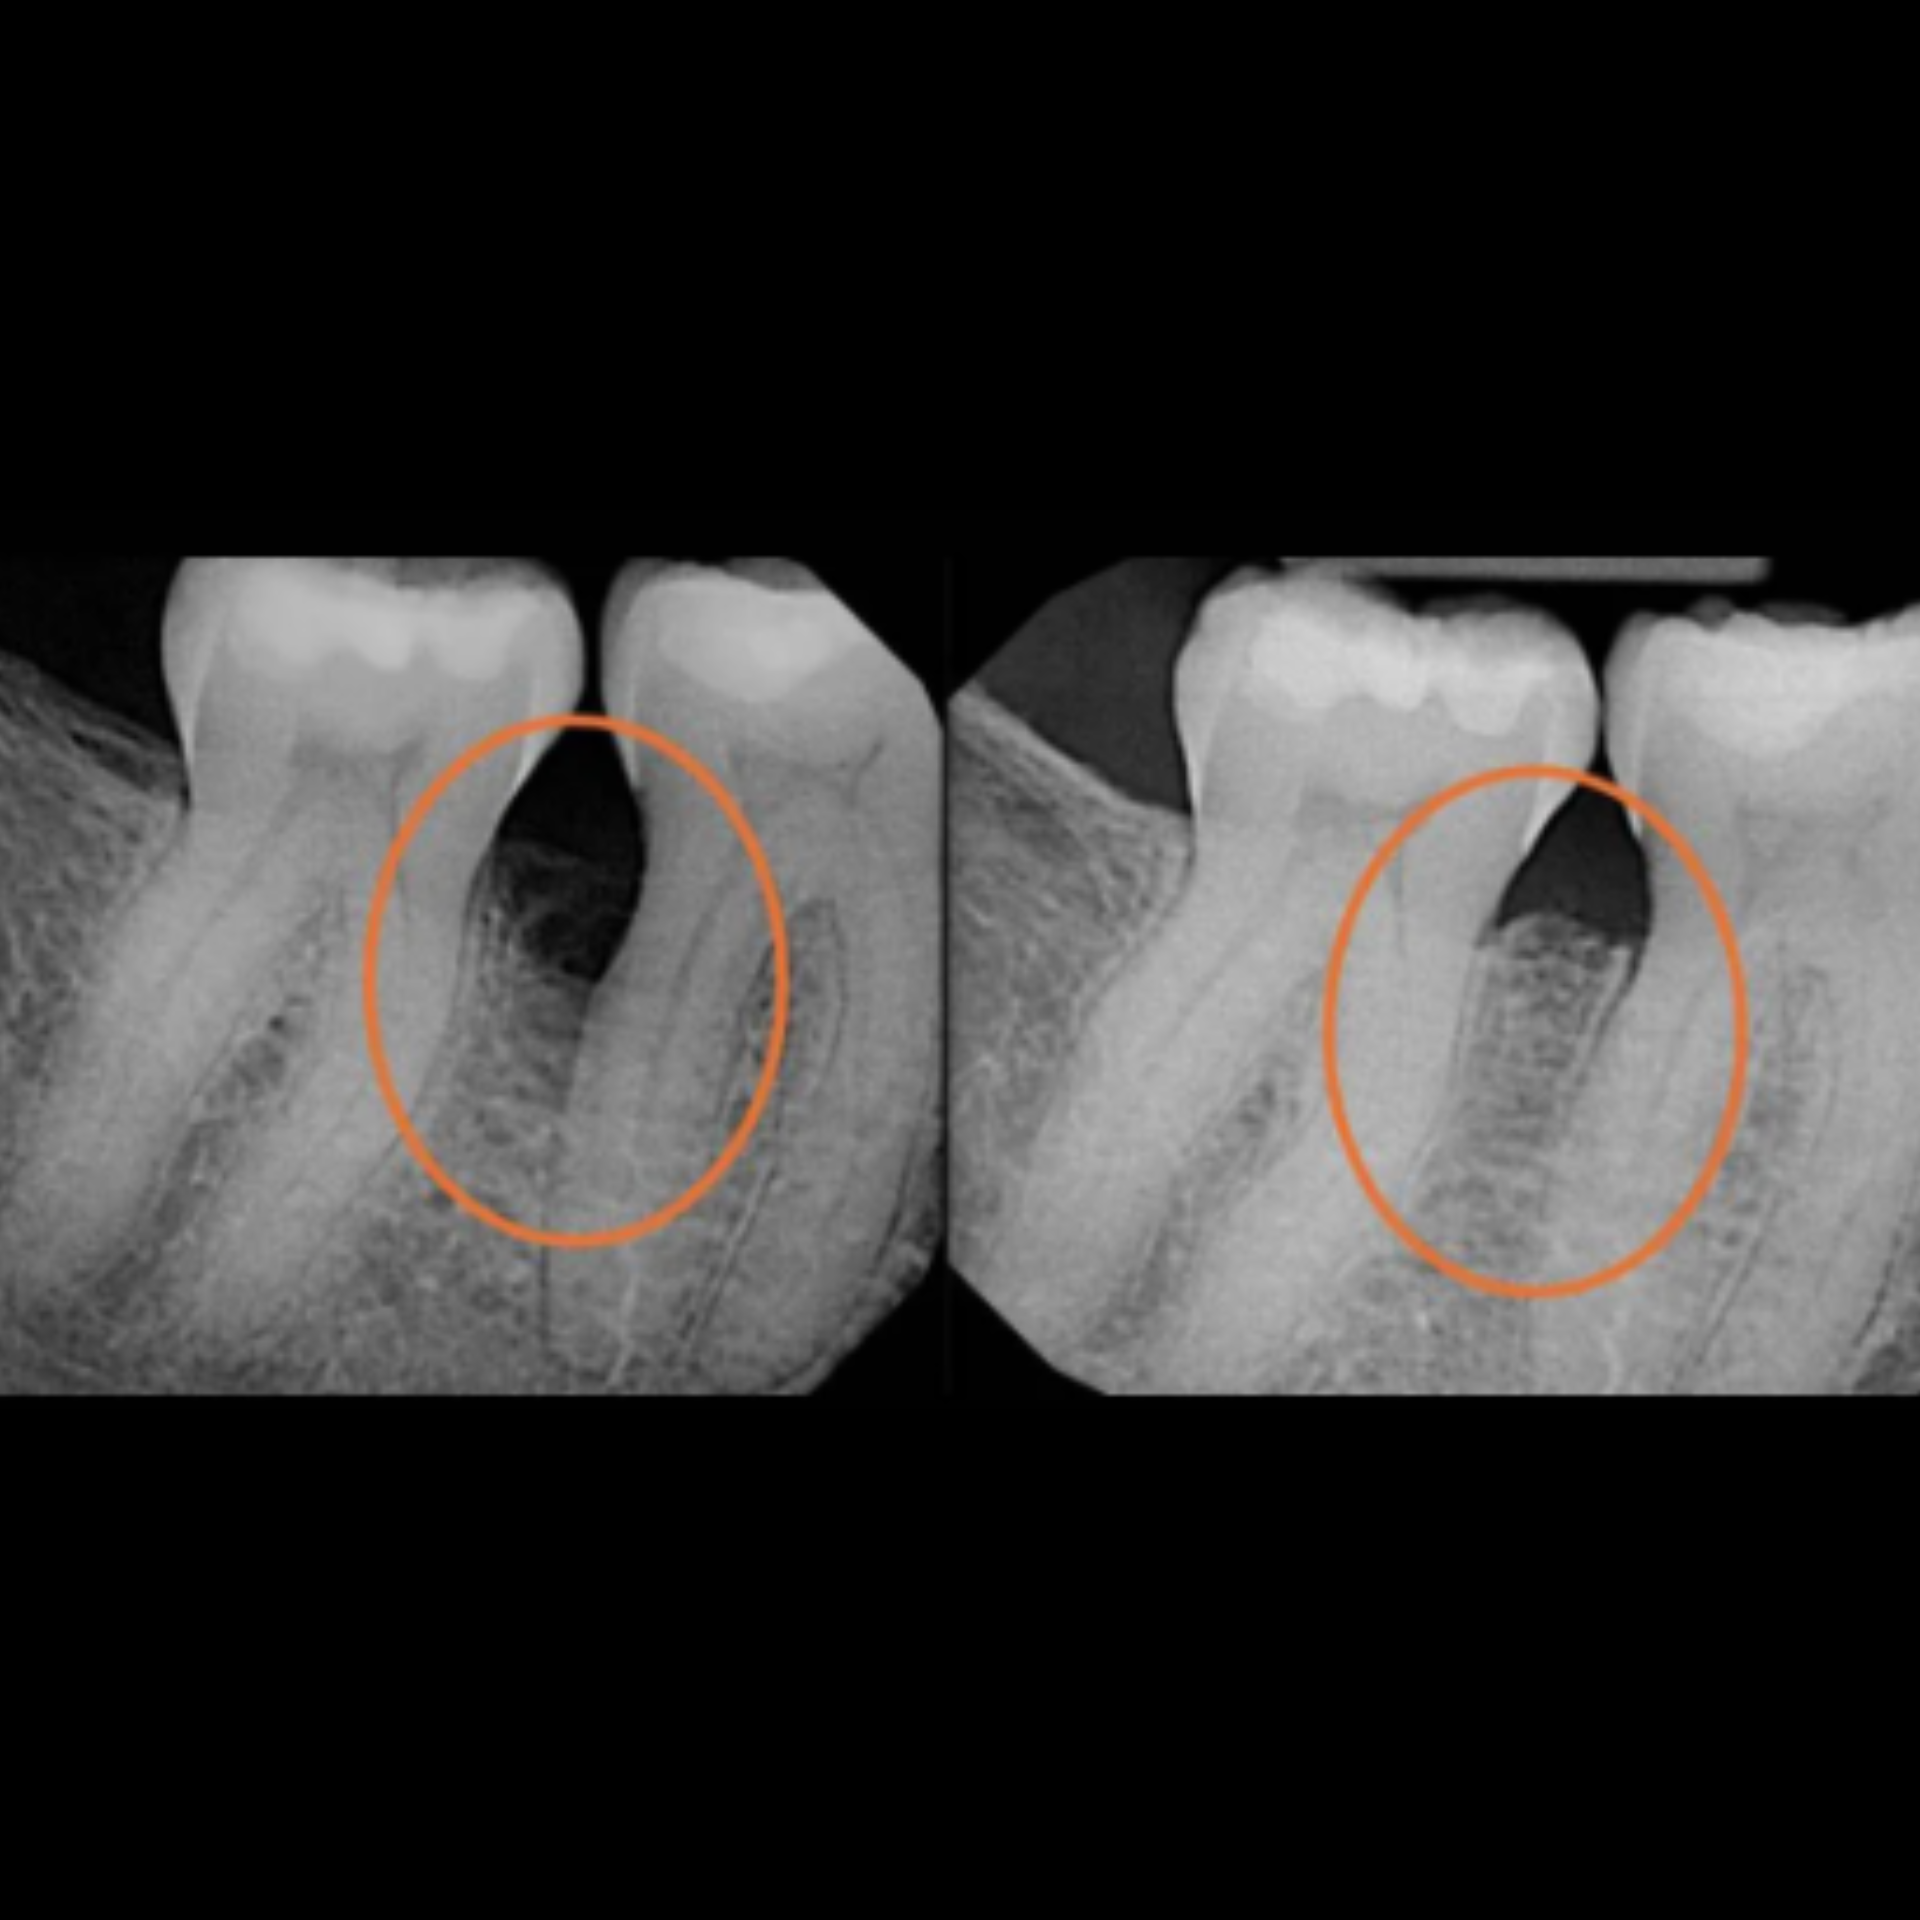

At Elite Dental Group, we provided emergency care that included root canal treatment on the upper central incisors. Dr. Satish Palayam performed an immediate implant placement for the right lateral incisor and completed a crown lengthening procedure on the palatal side of the right central incisor to support proper restoration. A provisional bridge was then placed to maintain both function and esthetics throughout the healing phase.

After a four month healing period, the final crowns were placed on the central incisors, and the implant for the right lateral incisor was successfully restored and finalized.